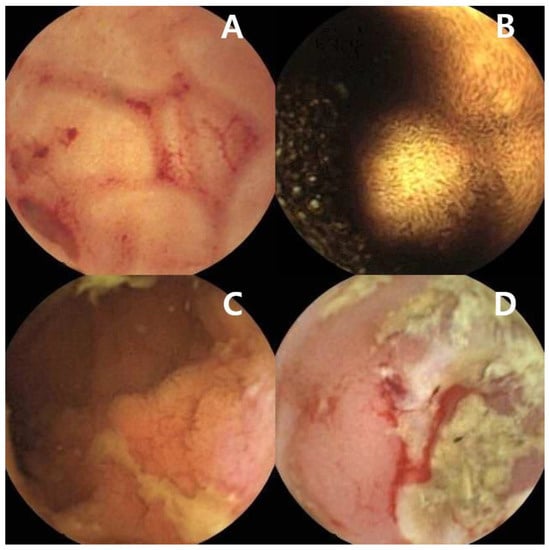

Despite standard bidirectional endoscopy, 30% of IDA patients are not definitively diagnosed [44]. When the standard examination results are negative, the small bowel may be considered the source of bleeding [5]. In the small bowel of IDA patients, lesions such as angioectasias, tumors, ulcers, or inflammatory lesions may be detected (Figure 2A–D) [45,46]. In a recent study by Olano et al., positive findings were present in 50% of patients with IDA; the most frequent finding was angiodysplasia [46]. According to a meta-analysis of CE in IDA patients, the pooled diagnostic yield was 66.6% when studies exclusively focused on patients with IDA were pooled [45]. However, in a recent guideline, the consensus group mentioned that the diagnostic yield of CE in unselected IDA patients is unlikely to change the long-term outcomes of patients with IDA, and CE can be considered for selected patients with more severe IDA (requiring transfusion, hemoglobin level < 10 g/dL), or recurrent or persistent IDA despite iron replacement) [47]. For patients with risk factors for small bowel malignancy, investigation of the small bowel should be considered [15,48]. Patients with FAP have an increased risk of duodenal adenomas and duodenal cancer; up to 90% of these patients have duodenal adenomas. The cumulative lifetime risk of duodenal cancer is 4–10% [15]. Duodenal polyposis needs to be assessed using upper GI endoscopy in patients with FAP. The surveillance interval is based on the Spigelman score [15,48,49]. Duodenal surveillance improved the prognosis of patients with FAP [50]. Patients with PJS have an increased risk of small bowel cancer (relative risk of 520; 95% confidence limits: 220, 1306) [51]; therefore, small bowel surveillance using CE or MRI is recommended every 1–3 years. For polyps larger than 15–20 mm in patients with PJS, elective polypectomy using DAE is recommended [15]. Some studies reported that although the diagnostic yield of small bowel lesions is significantly higher in the elderly [52], CE is also useful for the diagnosis of small bowel malignant lesions in younger IDA patients [53,54,55]. In a recent study of 220 patients with IDA (aged < 50 years) and negative bidirectional endoscopies, 32% of the patients had significant small bowel pathology, and 3.6% (N = 8) of the patients had a small bowel malignancy (four adenocarcinomas, three GISTs, and one lymphoma) [55]. Sidhu et al. concurred that the diagnostic yield of the younger group is lower than the diagnostic yield of the elderly, but significant lesions such as small bowel tumors are detected at younger ages, thus suggesting the usefulness of CE in the younger group [53]. The findings from Koulaouzidis et al.’s study showed that small bowel lesions of the elderly were mostly vascular lesions, such as angioectasia, but 25% of patients aged < 40 years had a sinister diagnosis of the small bowel including malignancy or Crohn’s disease [54]. In the same study, 10% of patients aged < 40 years were diagnosed with lymphoma. In a study by Johnston et al., small bowel malignancies were confirmed in seven patients (two adenocarcinomas, two GISTs, two lymphomas, and one jejunal metastasis from a lung sarcoma). The median age of the patients diagnosed with small bowel malignancies was 50 years; younger patients referred for IDA were more likely to have small bowel malignancies [56]. Considering the increased risk of complications in the elderly, it is important to determine which potential benefits might be expected from these investigations and discuss the possible therapeutic plan [37]. In a previous study of IDA patients older than 80 years, omission of additional diagnostic workup seemed appropriate in the presence of significant comorbidities and limited life expectancy [57]. Elderly patients with unexplained IDA after bidirectional endoscopic exam had favorable outcomes [58]. Girelli et al. showed that performing CE in patients older than 80 years was troublesome, and a considerable proportion of the patients experienced CE failure [59]. Therefore, CE should only be performed in selected elderly patients [37].

Figure 2.

Small intestinal images captured by capsule endoscopy (A) Angioectasias of the jejunum. (B) Gastrointestinal stromal tumor of the jejunum. (C) Longitudinal ulcer of the ileum in a patient with Crohn’s disease. (D) Ileal ulcer with spontaneous bleeding in a patient with NSAID-induced enteropathy.